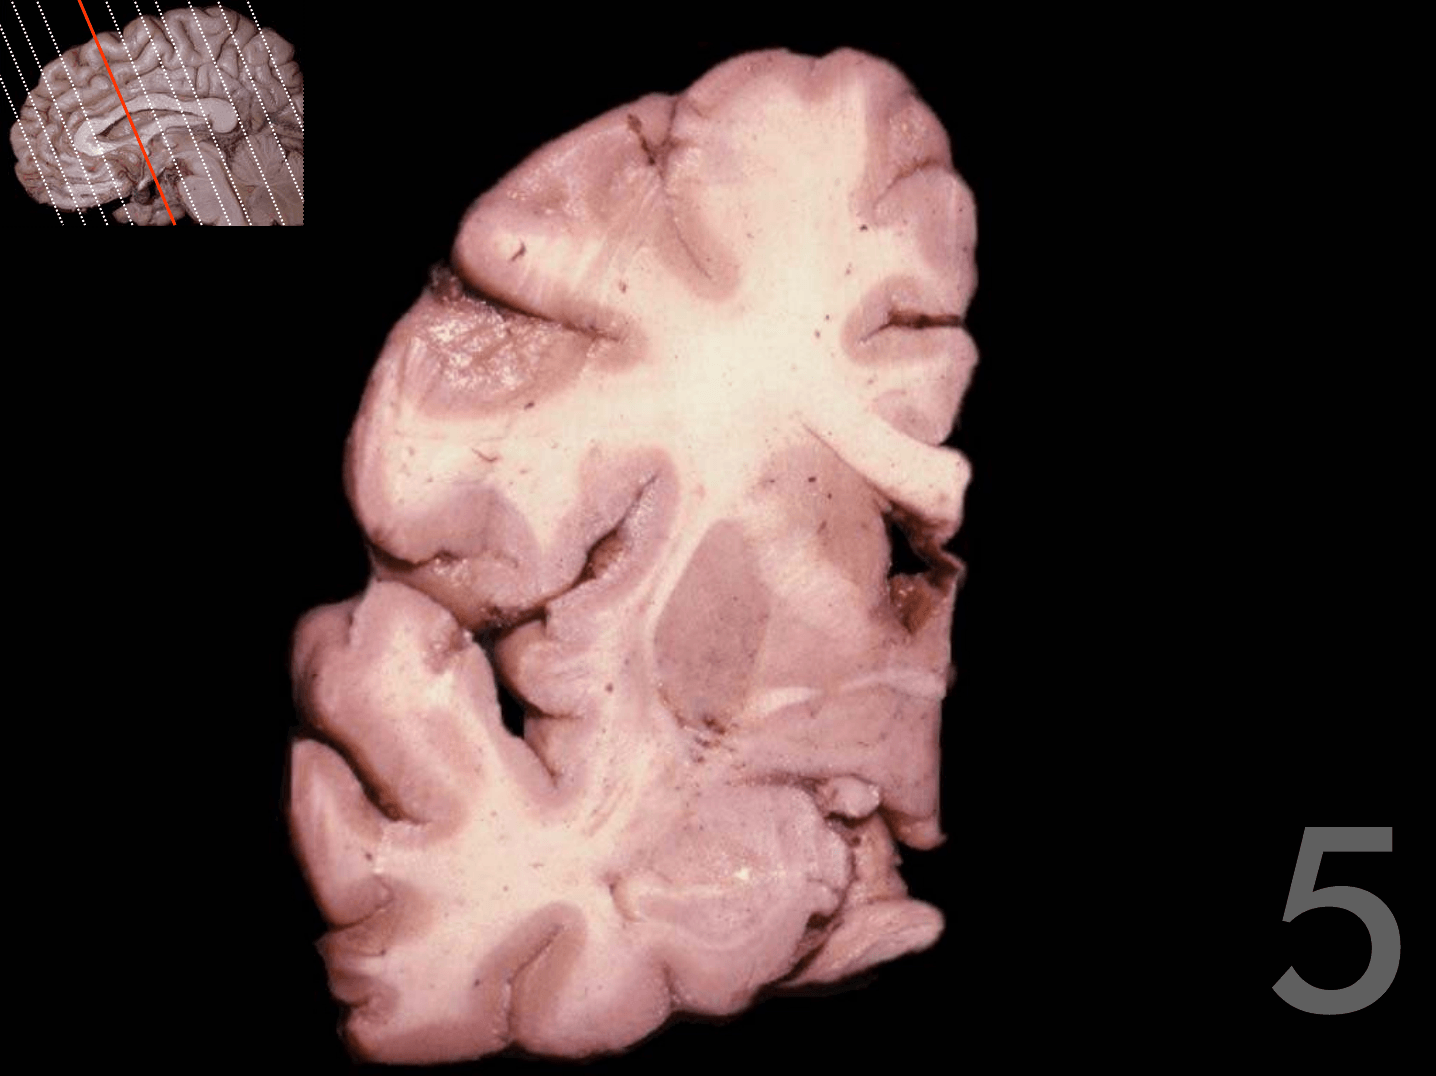

Tronco del cuerpo calloso

Rodilla del cuerpo calloso

Columna del fórnix

Comisura anterior

Foramen interventricular

Infundíbulo

Habénula

Pico del cuerpo calloso

Acueducto del mesencéfalo

Estría medular del tálamo

Adhesión intertalámica

Lámina terminal

Quiasma óptico

Tubérculo mamilar

Comisura posterior

Glándula pineal

Rodete del cuerpo calloso

Calota mesencefálica

Túber cinereum